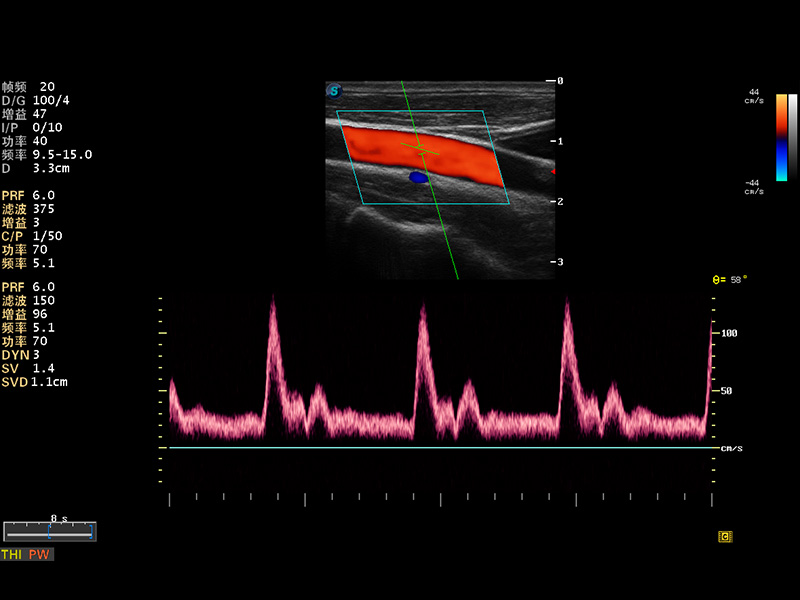

S8 EXP便携式彩色多普勒超声诊断仪是诸侯快讯官网研发的高端全身应用型便携彩超。高通道的VIS平台融合可视化(Visual)、智能化(Intelligent)和人性化(Smart)的特点,配以诸侯快讯官网自主研发生产的探头大家族,使您能够快速、准确的获得病人信息,提高工作效率的同时减轻疲劳。

多波束形成器